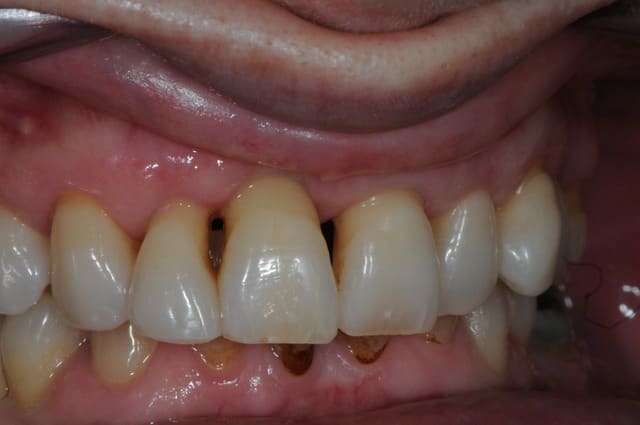

patiente 43 ans, très souriante, rigole tous le temps, fumeuse devant l'Eternel (1paquet/jour).

la parodontite et la mobilité sur 12 l'inquiète d'autan plus que les dents sont de plus en plus mobiles.

la 12 est perdue, mais également la 11 qui subit déjà une forte résorption gingivale.

21 et 22 pas beaucoup mieux.

on décide donc d'extraire 12-11-21-22, ROG, implantation et mise en charge immédiate. puis, chirurgie parodontal d'augmentation (surtout pour le secteur 11) et enfin bridge définitif avec chape en zircone. la patiente refuse catégoriquement une prothèse adjointe. elle est coquette